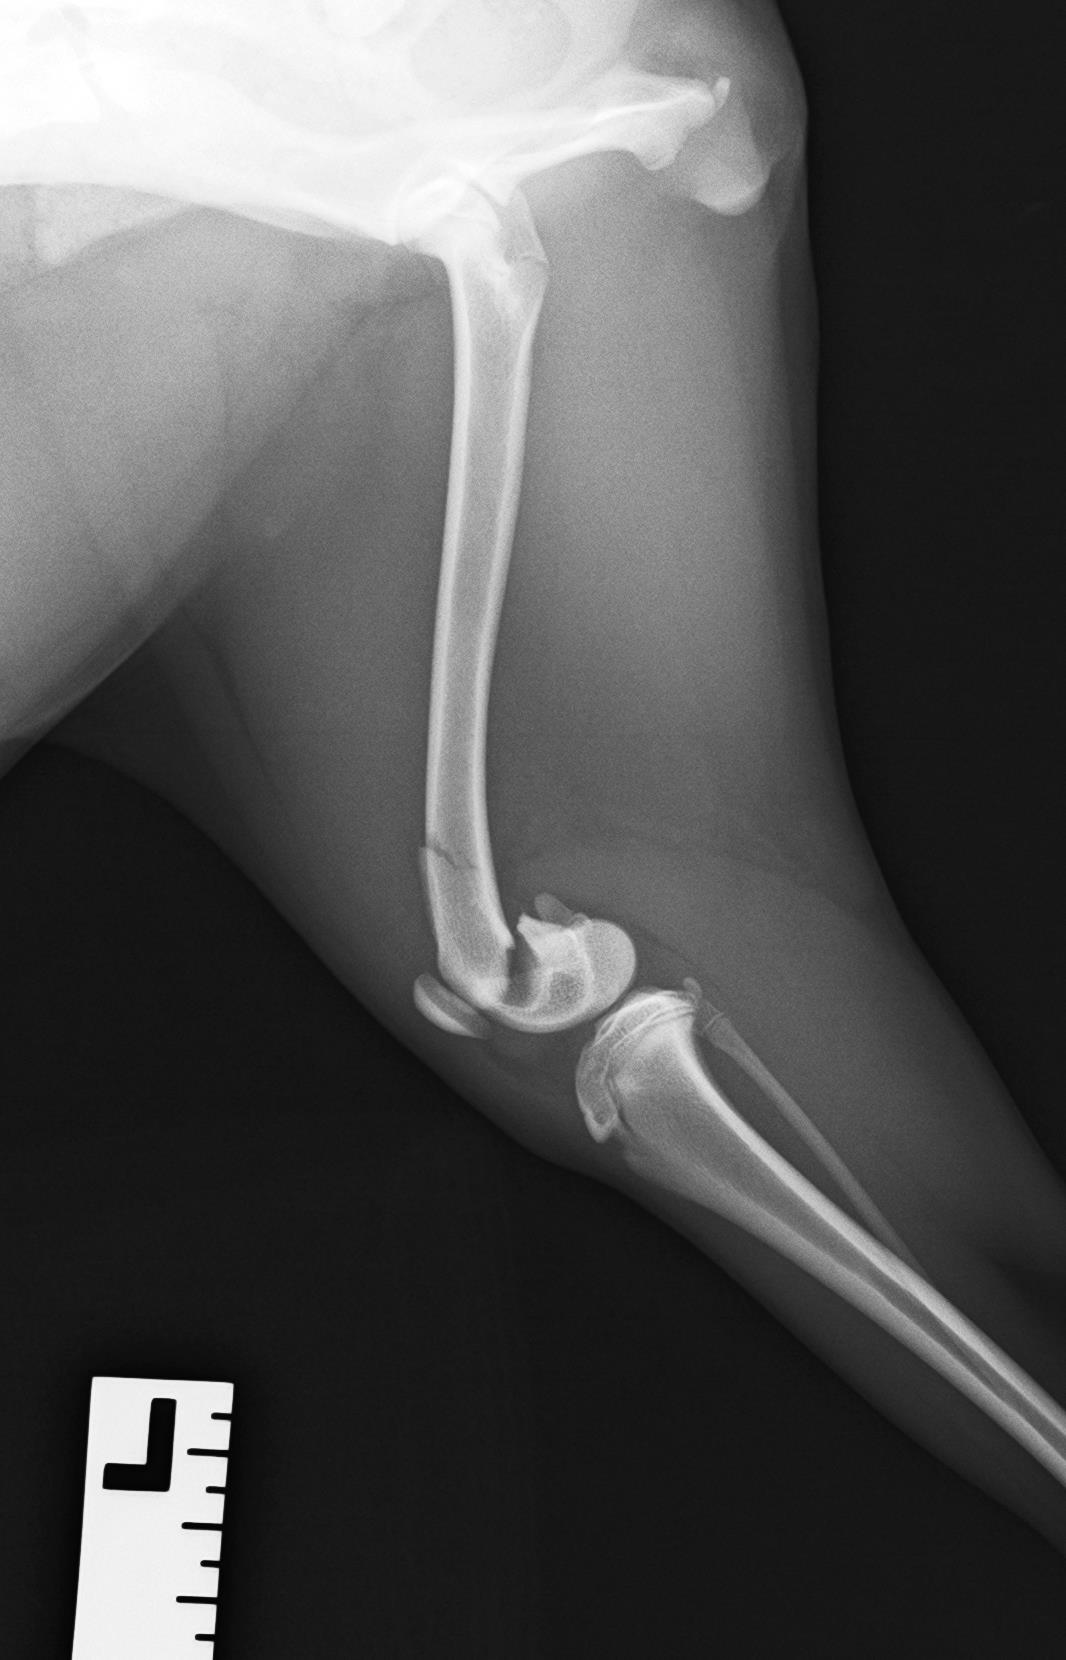

9ヶ月の柴犬の女の子が、高所から落下してしまい左後肢を痛めたとのことで来院されました。左後肢は足を着くことができず、レントゲン検査の結果、大腿骨(太ももの骨)の…